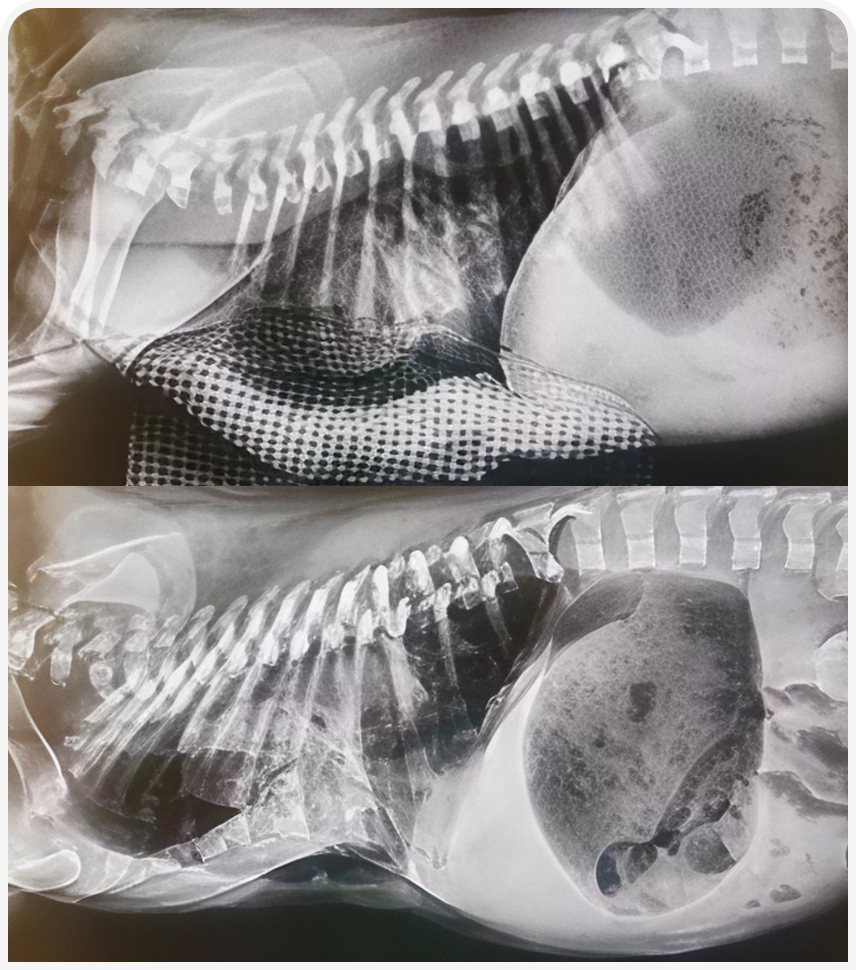

Врожденные аномалии развития. Статья из книги «Неонатология и педиатрия собак и кошек»

«Врожденные аномалии развития »!